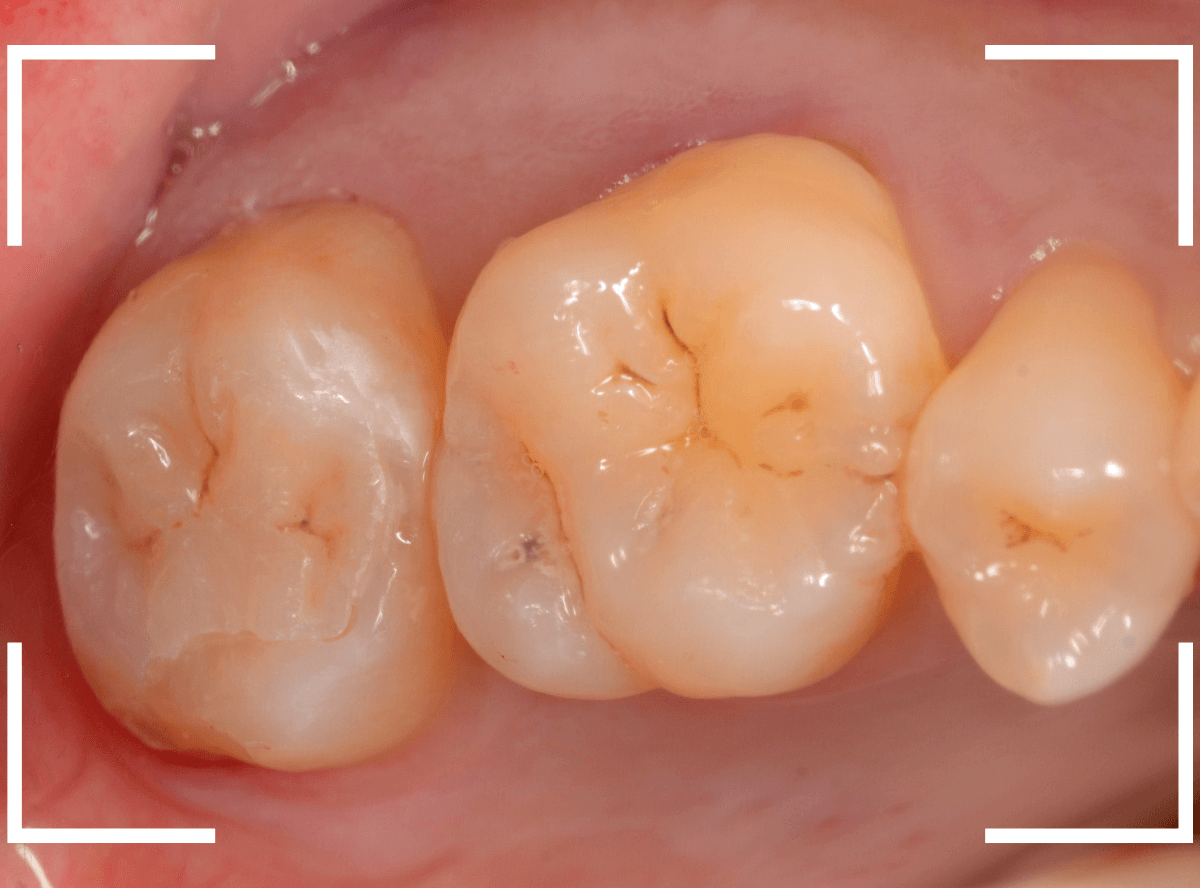

Case.30 上の奥歯のセラミック治療

メンテナンス中に、虫歯が見つかった方のケースです。

大きな虫歯でしたので、しばらく経過観察しましたが、特に症状もありませんでしたので、患者さんの希望に伴い、ジルコニア・インレーで治療をします。

セラミックが精密にsetできるように、歯をトリミングします。

模型上で精密に製作します。

治療後の状態です。

ジルコニア・インレーはE-MAX・インレーより審美性に劣るのですが、患者さんにもご満足いただける仕上がりになり、ホッとしました。